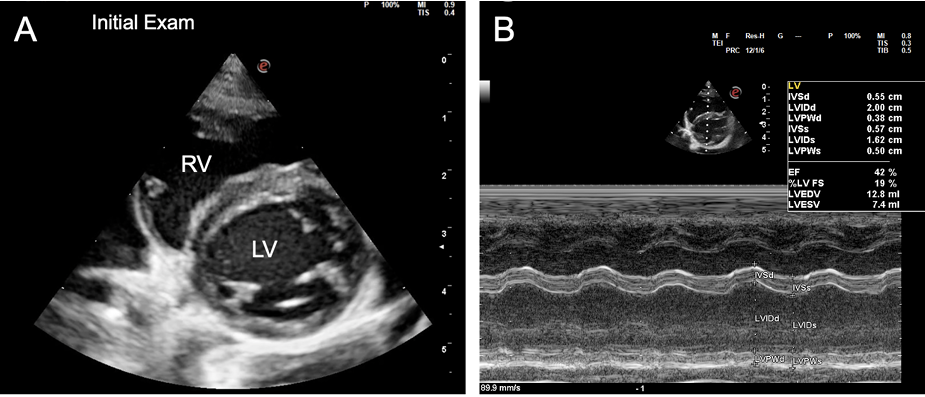

이번 연구는 1.5살의 중성화 암컷 고양이에 대한 증례 보고입니다. 해당 고양이는 이틀간의 기력 저하, 식욕 부진, 호흡 곤란 증상으로 내원하였습니다. 응급 초음파 검사에서 다량의 흉수와 소량의 복수가 확인되었고, 심장 초음파 검사를 통해 양심실 및 양심방 확장과 심수축력 저하를 특징으로 하는 확장성 심근병증(DCM) 표현형 및 울혈성 심부전이 진단되었습니다. 타우린 수치는 정상이었으며, 감염병 검사에서 Bartonella spp. 에 대한 항체(IgG)가 높게 측정되었습니다. 이에 따라 울혈성 심부전 치료(피모벤단, 푸로세마이드, 클로피도그렐)와 의심되는 바르토넬라증에 대한 항생제 치료(프라도플록사신, 독시사이클린)가 병행되었습니다.

- 초기 진단: 환자는 심각한 울혈성 심부전 상태였으며, 심장 초음파 검사상 심장이 전반적으로 확장되고 수축 기능이 현저히 저하된 전형적인 DCM의 모습을 보였습니다.

- 치료 후 심장 기능의 회복: 심부전 치료와 항생제 치료를 시작한 후, 2.5개월, 5개월, 9개월 차에 진행된 추적 심장 초음파 검사에서 놀라운 변화가 관찰되었습니다. 확장되었던 심방과 심실의 크기가 정상 범위로 줄어들고, 저하되었던 심실 수축 기능 또한 정상으로 회복되는 '역 리모델링(reverse remodeling)'이 명확하게 확인되었습니다.